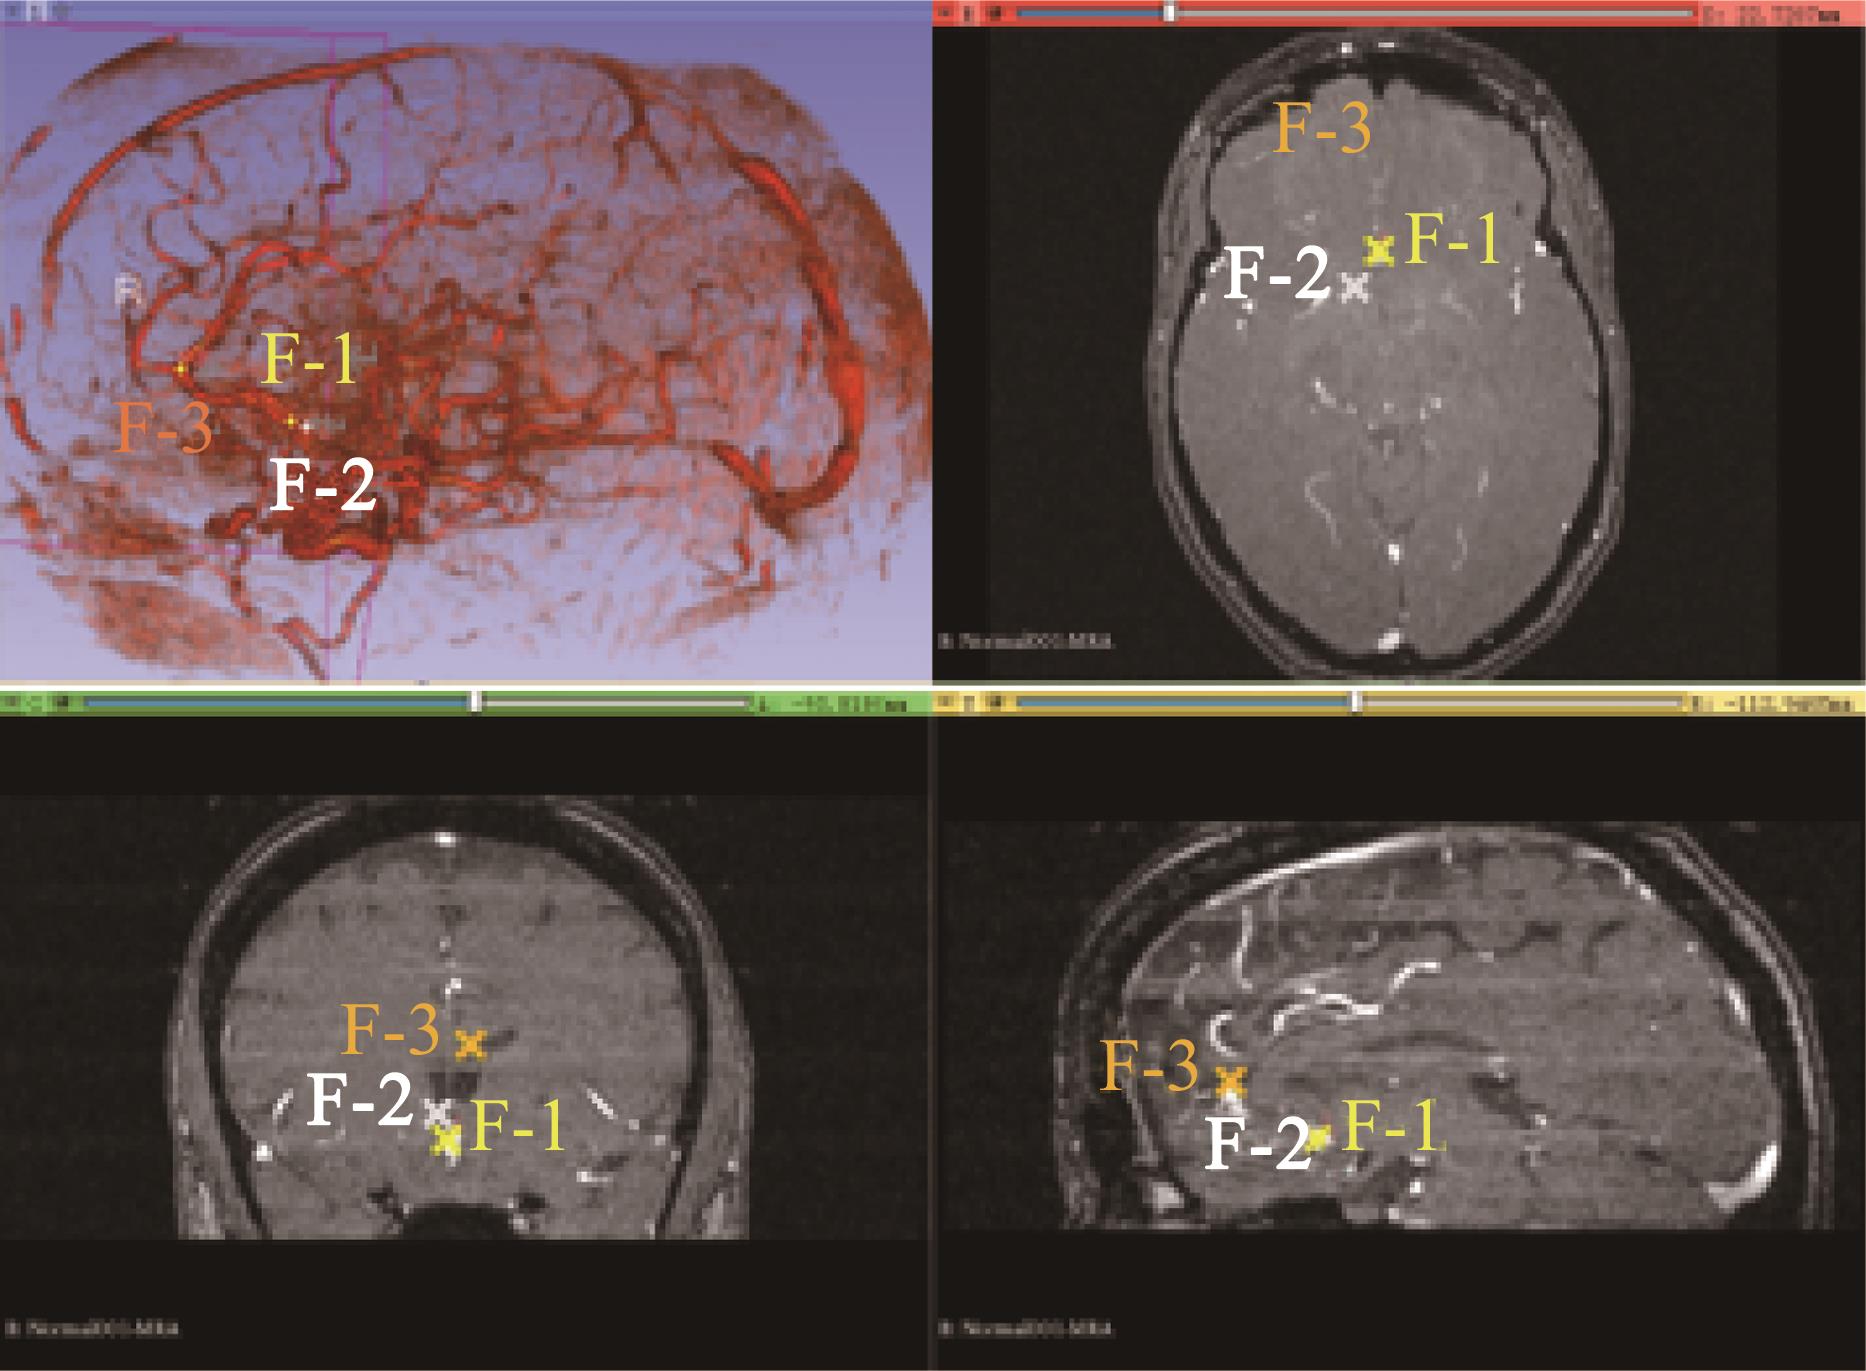

Localization results of cerebrovascular intervention

| 点位编号 | x | y | z |

|---|---|---|---|

| 1号点 | -1.295 0 | 0.618 0 | 2.272 0 |

| 计算结果 | -1.282 9 | 0.588 6 | 2.239 9 |

| 误差 | 0.012 1 | -0.029 4 | -0.032 1 |

| 2号点 | -1.397 0 | 0.869 0 | 2.558 0 |

| 计算结果 | -1.389 3 | 0.839 0 | 2.544 1 |

| 误差 | 0.007 7 | -0.030 0 | -0.013 9 |

| 3号点 | -1.192 0 | 2.907 0 | 3.362 0 |

| 计算结果 | -1.188 5 | 2.914 9 | 3.329 2 |

| 误差 | 0.003 5 | 0.007 9 | -0.032 8 |